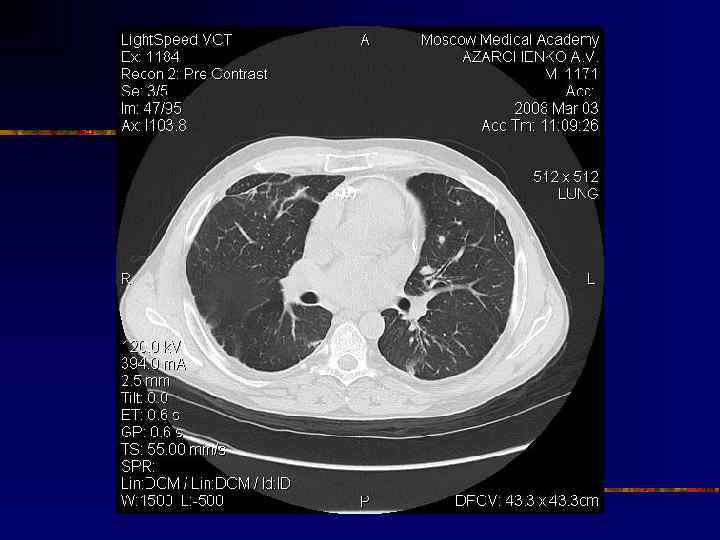

Кальциноз перикарда